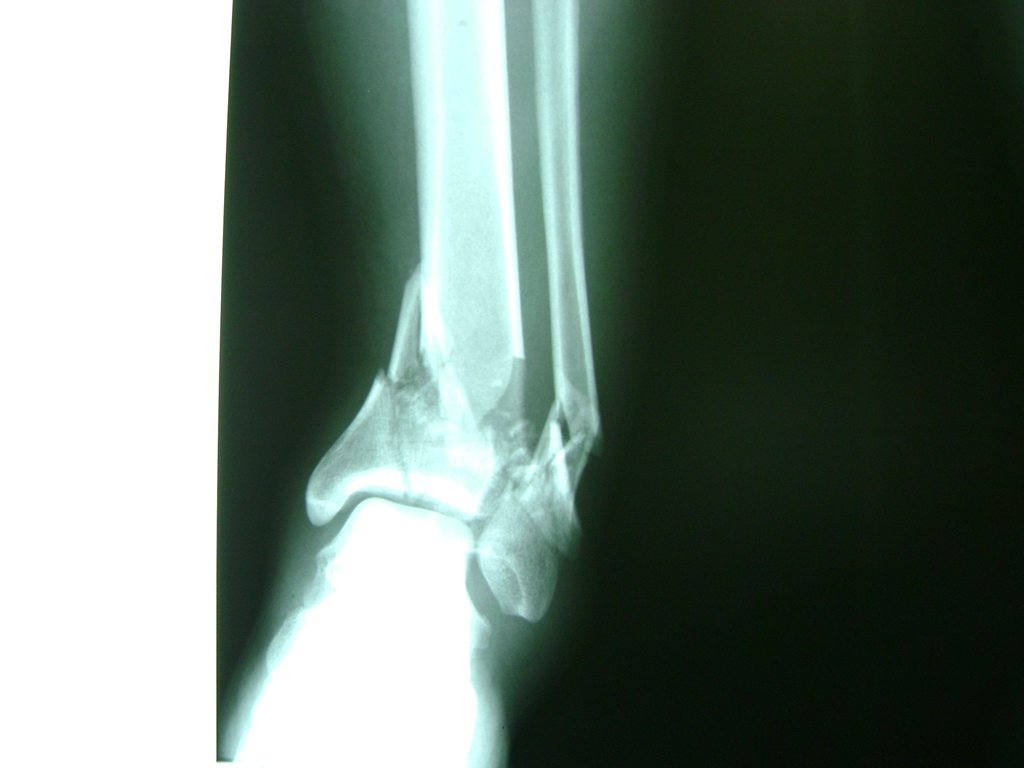

Algunas fracturas de tobillo pueden requerir cirugía si:

- Los extremos de los huesos están desalineados entre sí (desplazados).

- La fractura se extiende hasta la articulación del tobillo (fractura intra-articular).

- Los tendones o ligamentos (tejidos que sujetan los músculos y los huesos entre sí) están rotos.

- El médico cree que sus huesos probablemente no sanen apropiadamente sin cirugía.